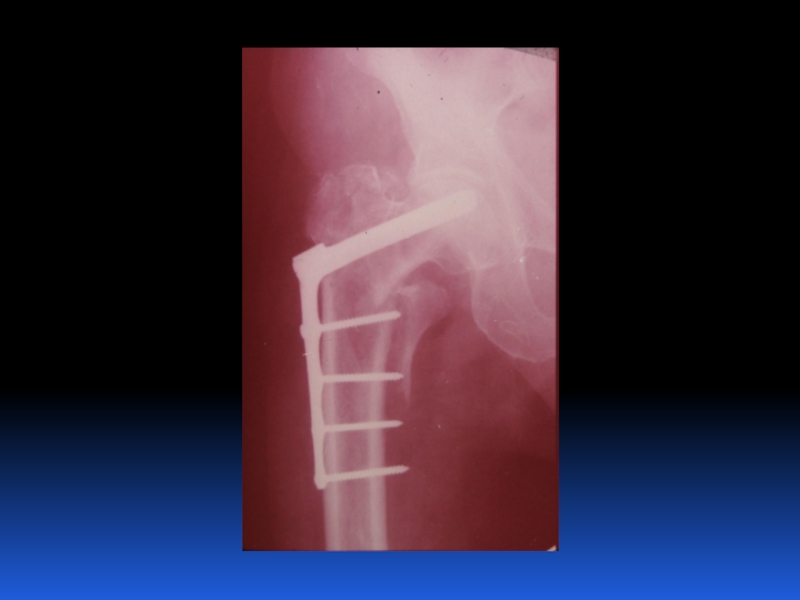

Остеопороз – это системное заболевание скелета, характеризующееся снижением костной массы и нарушением микроархитектоники костной ткани, с последующим увеличением хрупкости костей, со склонностью к патологическим переломам.

Слайд 2 Остеопороз – это системное заболевание скелета, характеризующееся снижением костной

массы и нарушением микроархитектоники костной ткани, с последующим увеличением хрупкости

костей, со склонностью к патологическим переломам.